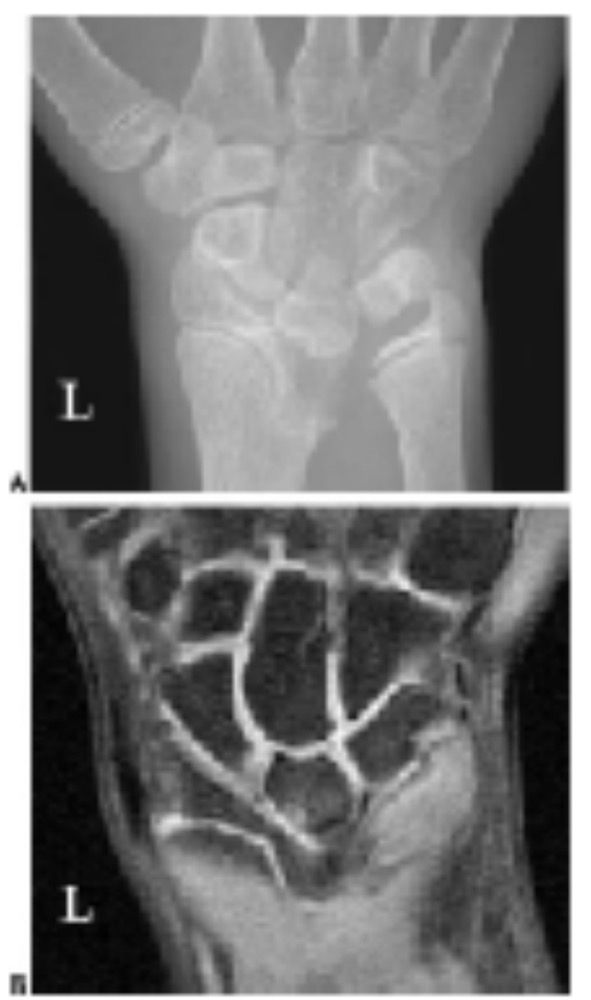

图9. 一名14岁女孩的左手腕马德隆畸形.

在(A) 可见桡骨远侧生长部内侧过早融合,(B)为相应的磁共振图像。

可见远侧桡尺关节的腕骨楔入和远侧尺骨的背向半脱位,腕骨角度减小和近侧腕骨的半脱位。